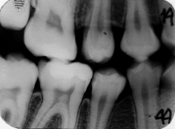

- leziune initiala de smalt situata pe fata distala a dintelui 4.5, vizibila ca arie triunghiulara intunecata in externa a smaltului pe radiografia bitewing.